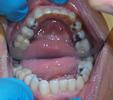

Invisalign

Invisalign orthodontics on the lower dental arch.